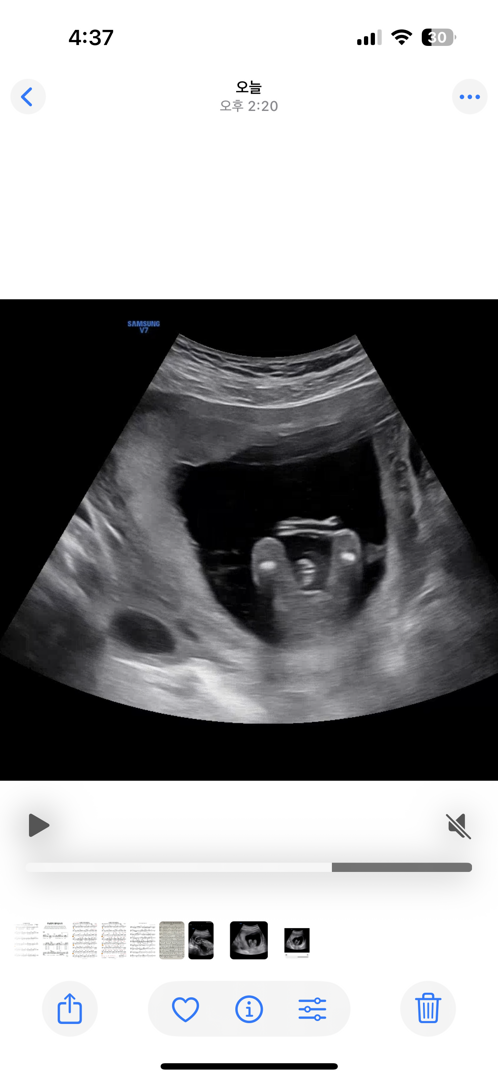

15주 초음파 도와주세요ㅠㅠ

다리 사이로 얼굴 척추뼈에 탯줄까지 .. 자꾸 엉켜서 보이니까 확실하지 않다고 한달 뒤에 보자고 하시네요ㅠㅠ 사진 댓글로 더 올릴텐데 한번만 도와주세요유ㅠㅠ